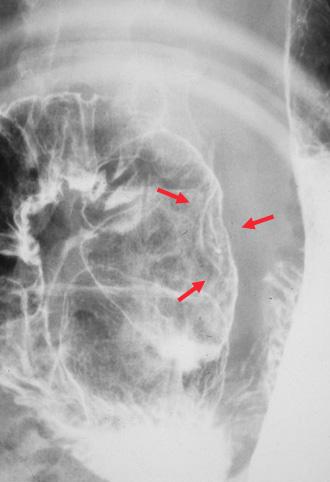

症例提示(所在地,施設名等): 福岡県・ 九州大学病院 (宮坂先生からの提供症例)

疾患(病理主体)の分類腫瘍様病変/異所性粘膜

部位(臓器別)十二指腸/球部

検査方法X-P

病変の最大径(ミリ)15〜19